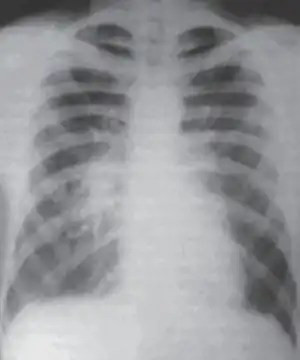

CXR of atypical pneumonia showing right central peribronchial infiltrate

Atypical pneumonia- Chest x-ray, dense infiltration in the left lower lobe

Chest X-rays often show a lung infection before physical signs are observable.[11] This is occult pneumonia. In general, occult pneumonia is rather often present in patients with pneumonia and can also be caused by Streptococcus pneumoniae, as the decrease of occult pneumonia after vaccination of children with a pneumococcal vaccine suggests.[18][19]

Infiltration commonly begins in the perihilar region (where the bronchus begins) and spreads in a wedge- or fan-shaped fashion toward the periphery of the lung field. The process most often involves the lower lobe, but may affect any lobe or combination of lobes.[11]